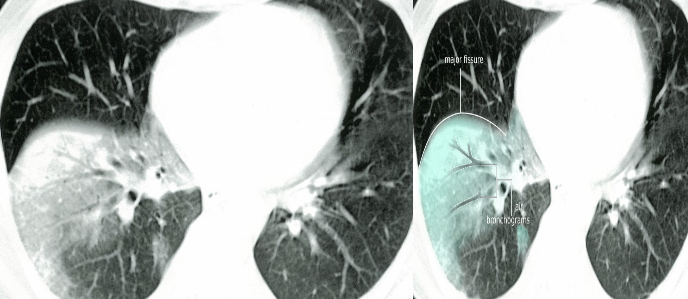

IMAGING

- CXR:

- The appearance of consolidation on CXR is reliable for the diagnosis of pneumonia, but CXR appearances are not reliable for distinguishing between viral and bacterial infection as there is considerable overlap.

- The CXR may appear normal early in the disease. However, as an approximate guide:

- Viral pneumonia:

- Patchy perihilar infiltration, hyperinflation, atelectasis

- Bacterial pneumonia:

- Lobar consolidation (air bronchogram) occasionally with parapneumonic effusion. Pneumatocoele and abscesses suggest staphylococcal pneumonia

- Mycoplasma pneumonia: most commonly school age

- Patchy, segmental consolidation with hilar lymphadenopathy.

- Viral pneumonia:

Chest X-Ray showing patch of pneumonia

Image of chest x-ray displaying the interstitial pattern seen in viral pneumonia. The interstitial pattern shows fine lines radiating from the hila.

These chest X rays compare clear, healthy lungs with the cloudy, inflamed lung tissue of pneumonia.

Right lower lobe consolidation in a patient with bacterial pneumonia.

Imaging

RT. lower lobe; Lobar pneumonia: Opacity of one or more pulmonary lobes & Presence of air bronchograms

- Right lower lobe is most commonly affected by pneumonia

- Spine blackness increased reversibly (Spine sign); lower part opaque

Bronchopneumonia:

- Poorly defined patchy infiltrates scattered throughout the lungs.

- Presence of air bronchograms

Air Bronchogram

Normally, it is not possible to identify air in bronchi within normally aerated lung, because the walls of the normal bronchi are too thin and air-filled bronchi are surrounded by air in the alveoli. However, if the alveoli are filled with fluid, the air in the bronchi contrasts with the fluid in the adjacent lung.

CT chest (axial plane; lung window) of a patient with a history of bacterial pneumonia

Opacification of much of the right lower lobe parenchyma is the result of air space consolidation. Pulmonary vessels are obscured and patent airways

(air bronchograms, white dashed line) are seen.